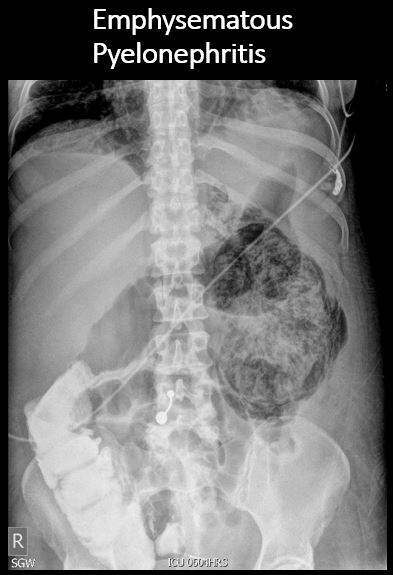

There is renal or ureteral associated air. [Yes/No]